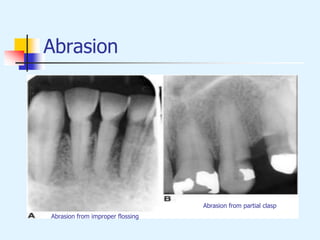

Abrasion

 Variety of patterns, depending on the cause

 Toothbrush abrasion presents as horizontal

cervical notches on buccal surface of exposed

radicular cementum and dentin; degree of loss

greatest on prominent teeth

 Thread-biting, pipe stem, bobby pins etc.,

produce rounded or V-shaped notches in incisal

edges of anterior teeth

 Dental floss, toothpicks result in loss of

interproximal radicular cementum and dentin

Abrasion from improper flossing

Abrasion from partial clasp